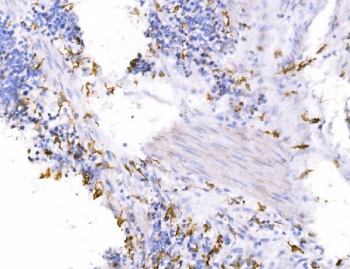

IHC staining of FFPE human gastric cancer tissue with Endophilin A1 antibody. HIER: boil tissue sections in pH8 EDTA for 20 min and allow to cool before testing.